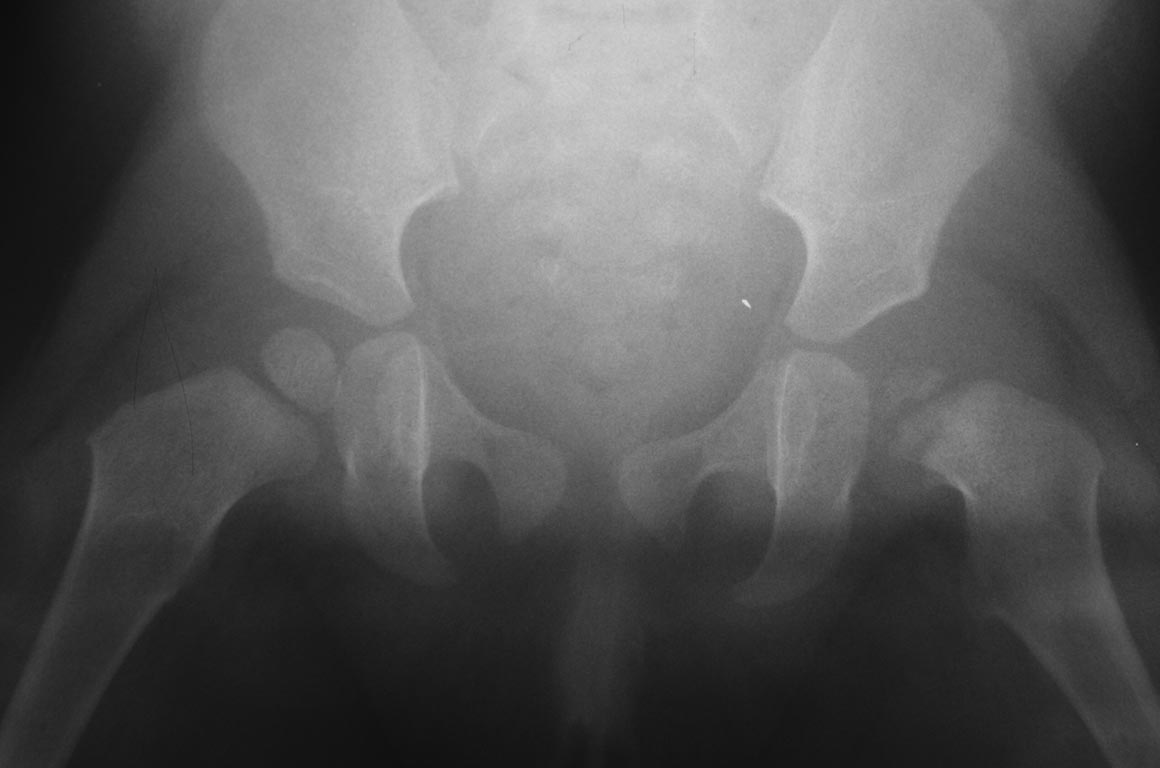

[Ortho] Острый гематогенный остеомиелит головки бедра и ребенка

Добрый вечер уважаемые коллеги. Помогите советом, в какую клинику и к

кому обратится с данной проблемой( у ребенка в возрасте 1мес.

диагностирован гематогенный остеомиелит головки бедра). Лечили

консервативно( выписку и фото в динамике прилагаю). На сегодняшний день

ребенку 11 мес. Детские ортопеды по месту сомневаются в тактике( в плане

операции или выжидательная тактика). Хотелось проконсультироваться с

теми кто занимается этой проблемой. Заранее спасибо.